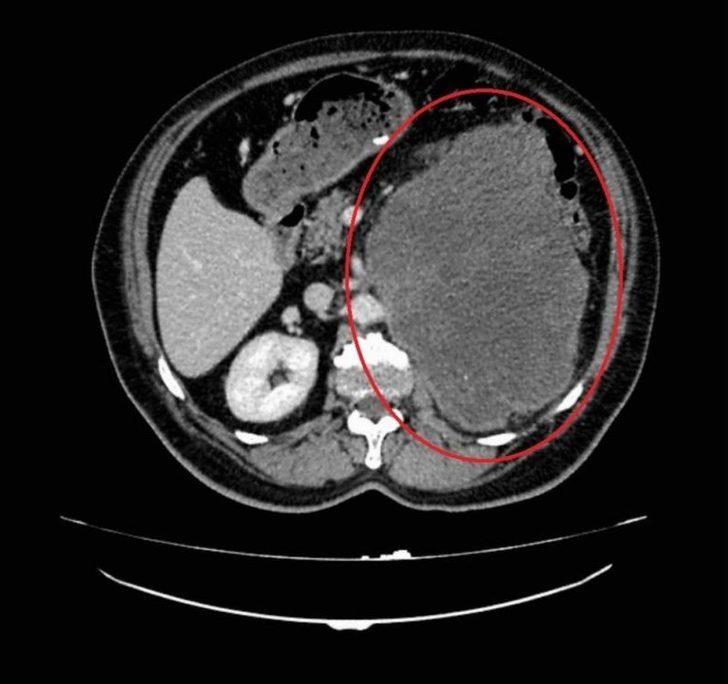

Ondokuz Mayıs Üniversitesi(OMÜ) Tıp Fakültesi Hastanesinde böbrekten çıkarılan 20 santim boyutundaki kitle, dünyada böbrekte ikinci kez rastlanan kötü huylu tümör (miksofibrosarkom) olarak literatüre geçti.Samsun’da 62 yaşında erkek hasta sol yan ağrısı ve karın şişliği şikayetleri ile OMÜ Tıp Fakültesi Hastanesi Üroloji Kliniğine başvurdu. Hastanın yapılan muayene ve tetkikleri sonucunda böbreğinde 20 santim boyutunda tümör tespit edildi. Başarılı bir ameliyatla çıkarılan kitlenin patoloji sonucu miksofibrosarkom olarak saptandı. Normalde kol ve bacaktaki yumuşak dokulardan kaynaklanan bu tümör türünün böbrekte görülmesine oldukça şaşırdıklarını belirten OMÜ Tıp Fakültesi Üroloji Anabilim Dalı Öğretim Üyesi Doç. Dr. Berkan Reşorlu, olgularını 2015 yılında İspanya’da görülen vakanın ardından dünyada görülen ikinci vaka olarak ürolojinin prestijli dergilerinden birinde yayınlattıklarını belirtti."Böbrekten kaynaklanmasını beklemiyorduk"Yapılan operasyon ve hasta hakkında bilgi veren Doç. Dr. Berkan Reşorlu, "Hastamız sol yan ağrısı ve karında şişlik şikayeti ile bize başvuran 62 yaşında bir erkekti. Yaptığımız muayene ve radyolojik görüntülemeler sonucunda sol böbrekten kaynaklanan 20 santim boyutunda bir kitle olduğunu tespit ettik. Bunun üzerine hastayı ameliyata alarak, başarılı bir operasyonla böbrekle birlikte kitleyi çıkardık. Çıkardığımız kitlenin patoloji sonucu sıklıkla kol ve bacaktaki yumuşak dokulardan kaynaklanan ’miksofibrosarkom’ dediğimiz kötü huylu bir tümör olarak geldi. Böyle bir tümörün böbrekten kaynaklanmasını beklemiyorduk. Literatürü araştırdığımızda böbrekten kaynaklanan tek ’miksofibrosarkom’ vakasının 2015 yılında İspanya’dan bildirildiğini gördük. Bunun üzerine bizde olgumuzu hızlı bir şekilde ürolojinin prestijli dergilerinden birinde yayınlattık ve dünyada görülen ikinci vaka olarak literatüre kazandırdık. Hastamızın kitlesi oldukça büyük, çevre organlara yapışık ve ana damarları tamamen sarmış durumdaydı. Oldukça riskli ve zor bir ameliyatın ardından bu kitleyi çıkartarak kemoterapi tedavisine başladık ve şu an hastamızı yakın takip altında tutuyoruz. Böbrek tümörleri, ürolojide prostat ve mesane kanserlerinin ardından en sık izlenen 3. kanser türü ve son yıllarda görülme sıklığı tüm dünyada artıyor. Tüm kanserlerde olduğu gibi bunlarda da erken tanı oldukça önemli. Ancak bu kanser türü sıklıkla tesadüfen saptanıyor. Çünkü hastaların ancak yüzde 10-15’lik kısmında idrardan kan gelmesi, karında şişlik ya da yan ağrısı gibi şikayetlere yol açıyor. Kendilerinde bu tip belirtiler izleyen hastaların vakit kaybetmeden bir üroloji uzmanına başvurmasını öneriyoruz" dedi."Patoloji sonucu bizi oldukça şaşırttı"Hastadan çıkarılan kitlenin oldukça büyük, çevre organ ve dokulara yapışık ve ana damarları tamamen sarmış olduğunu belirten Dr. Reşorlu, daha önce de bu tip kitleleri çıkardıklarını ancak patoloji sonucunun miksofibrosarkom olarak gelmesinin kendilerini de oldukça şaşırttığını sözlerine ekledi.